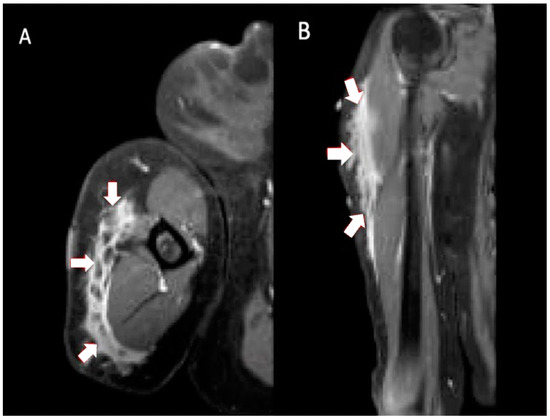

Figure 2. Multiplanar MRI of left shoulder taken 10 months after vaccine administration in left shoulder. Axial T1 weighted (A) image shows predominately intramuscular edema within the lateral deltoid muscle measuring 5.6 cm anterior-posterior and 1.0 cm medial-lateral (arrows). Coronal T1 weighted (B) image shows intramuscular edema within the lateral deltoid muscle measuring 10.0 cm proximal-distal (arrows). Axial T2 STIR (C) and coronal T1 weighted (D) images show a slightly enlarged left axillary node (9.9 × 11.2 × 12.8 mm) (arrows).

Three months after visiting the initial orthopedist, the patient attended a different orthopedic clinic to address the masses. At this visit, 10 months had passed since receiving her injections and the clinical examination showed normal range of motion with no tenderness to palpation. There were no rashes on inspection; however, edema and nodules to palpation were found in the lateral deltoid heads. Due to the persistent, previously unimaged left shoulder swelling, an MRI was performed, which showed similar findings of edema but in an intramuscular rather than subcutaneous location and the presence of a slightly enlarged axillary node (Figure 2). Ultimately, no biopsy or treatment was recommended on either side given the imaging findings and the improvement, albeit slow, in her symptoms and the swelling bilaterally. The patient’s symptoms had fully resolved when she returned after 2 months (1 year after completing the injections). Examination showed 5/5 deltoid strength bilaterally, full active range of motion without discomfort or crepitus, no visual deformities (swelling, effusion, erythema) in the distal upper extremities, and no joint tenderness on palpation.

Injection site granulomas were attributed to improper injection technique [15]. The intended location for COVID vaccination is intramuscular (IM), usually into the bulk of the deltoid muscle [5]. Injection site granulomas tend to occur in subcutaneous tissue (SC) and more frequently in females [15]. The depth of vaccine injections has a strong impact on tissue reaction. Deep IM injections are typically associated with fewer symptoms compared to SC or intradermal injections, possibly due to lower levels of nociceptors in muscle spindles compared with subcutaneous tissue and skin [16]. This likely accounts for the lower amount of swelling and pain on the patient’s left shoulder, where the imaging showed the reaction to be intramuscular, in contrast to the more symptomatic right shoulder subcutaneous reaction.